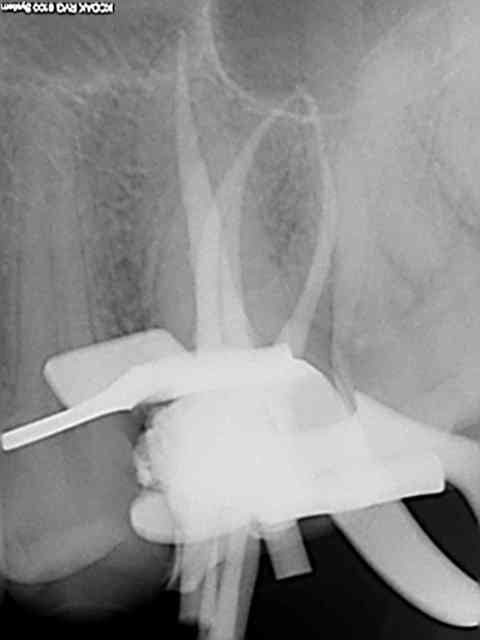

Et une de plus !

R19 vxiysf - Eugenol

R20 kboz6l - Eugenol

01 ukhwbq - Eugenol

C'est pas de la frime hein, mais ca fait plaisir d'avoir trouvé ENFIN une technique rapide et reproductible sans casse. (enfin presque il y a dans le tas un micro morceau de R25 pas loin de l'apex )